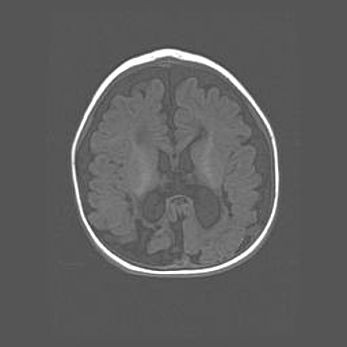

Открытая гидроцефалия.

Возраст: 9 месяцев 12 дней

Вес: 6800 г

Пол: мужской

Окружность головы: 41,5 см

Срок гестации: 28 недель

Гидроцефалия головного мозга у новорожденных имеет характерный признак: опережающий рост окружности головы приводит к визуально хорошо определяемой гидроцефальной форме сильно увеличенного в объёме черепа. Детские неврологи определяют следующие симптомы гидроцефалии у грудничков: выбухающий напряжённый родничок, частое запрокидывание головы, смещение глазных яблок к низу.